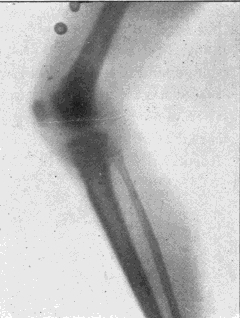

Fig. 1.—Head.

Fig. 2.—Broken Arm, Overlapping.

(Due to defective setting.)

Fig. 3.—Ribs.

Fig. 4.—Knee, Knickerbocker Buttons, Bullet in Femur.

FROM SCIAGRAPHS BY PROF. DAYTON C. MILLER. § 204.